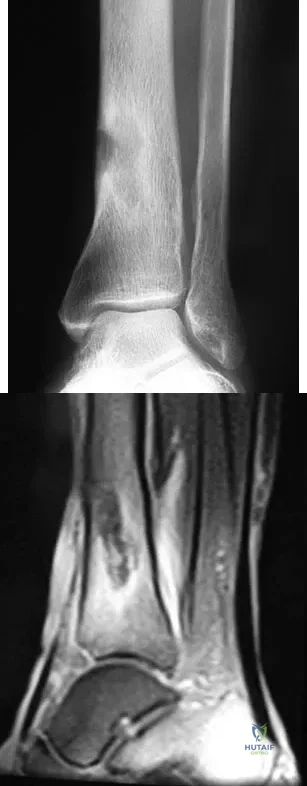

An 8-year-old boy with severe hemophilia A (factor VIII) and no inhibitor is averaging eight transfusions per month for bleeding into the right ankle. Examination shows synovial hypertrophy; range of motion consists of 0 degrees of dorsiflexion and 20 degrees of plantar flexion. The patient's knees, elbows, and left ankle have no restriction of motion. Standing radiographs of the right ankle are shown in Figure 18. Management should consist of

A 51-year-old man sustained an open fracture of his tibia in Korea 42 years ago. An infection developed and it was resolved with surgical treatment. For the past 6 months, an ulcer with mild drainage has developed over the medial tibia. The ulcer is small and there is minimal erythema at the ulcer site. A radiograph and MRI scan are shown in Figures 43a and Figure 43b. Initial cultures show Staphylococcus aureus susceptible to the most appropriate antibiotics. Laboratory studies show an erythrocyte sedimentation rate of 70 mm/h. What is the most appropriate surgical treatment at this time?

A 16-year-old snowboarder has significant pain and is still unable to bear weight after sustaining a lateral ankle injury in a fall 1 week ago. Examination reveals swelling and tenderness in the sinus tarsi. AP, lateral, and mortise radiographs of the ankle are unremarkable. Management should consist of